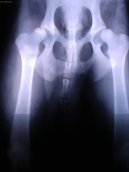

Kloubní potíže u psů se týkají z velké části vrozených vad a růstových poruch u mladých jedinců. Jedná se především o dysplazie kyčelních a loketních kloubů, poruchy tzv. osifikace rostoucích kostí, luxace kolenní čéšky apod.. U dospělých jsou to pak nejčastěji artrotické změny kloubů nejrůznějšího původu a poúrazové poškození např. kolenních vazů či nitrokloubní zlomeniny. Některé kloubní potíže lze řešit medikamentózní léčbou, jiné trvalým znehybněním kloubu. Pokud je to jen trochu možné, snahou ortopeda by mělo vždy být obnovení funkčnosti poškozeného kloubu, ve druhém sledu pak odstranění bolesti a zlepšení kvality života pacienta.

Obr.2: Artrotické změny na kyčelních kloubech 6 letého německého ovčáka s dysplazií. Tyto změny se vyvíjí postupně a až ve vyšším věku pacienta.

Dysplazie kyčelního kloubu je velmi častou vrozenou vadou u velkých a středních plemen. U většiny z nich se provádí povinné RTG vyšetření před uvedením do chovu.